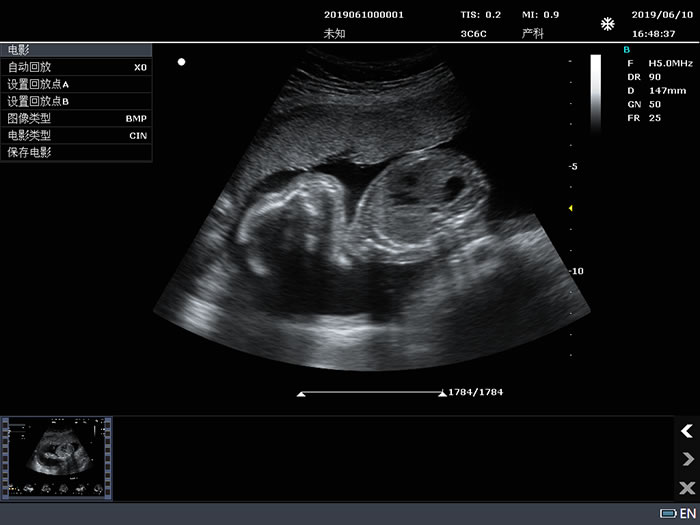

3C6C: 3.5MHz/R60/128阵元凸阵探头;

2.10 电影回放

2D模式,B最大: ≥5000帧,Color, PDI最大:≥2300帧;

时间线模式(M, PW), 最大:≥ 190s

支持JPG、BMP、FRM图像格式和CIN、AVI电影格式(AVI视频压缩倍率≥30);

产科B、PW模式应用测量:包括全面的产科径线测量、体重、单胎孕龄及生长曲线、羊水指数、胎儿生理评分测量等